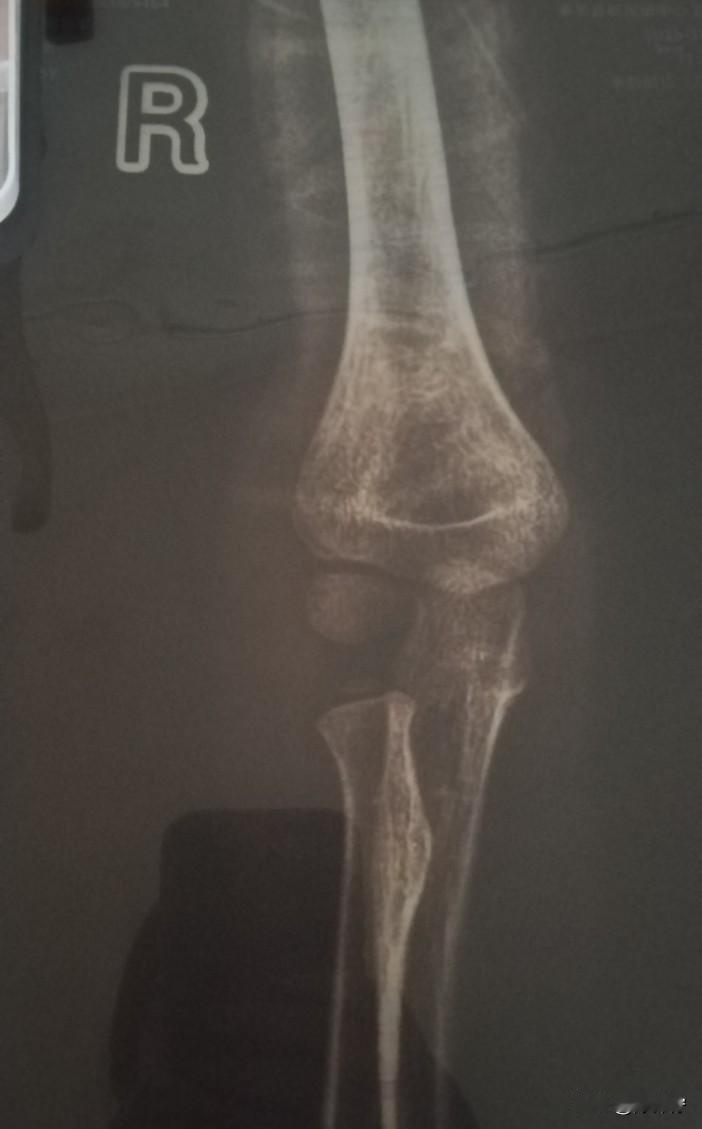

真是心疼死我了,早上去学校还是好好的,课间操老师就打电话来说“孩子出了事”,被同学撞到摔了”到学校一看孩子手臂都肿的老高,赶紧带孩子去医院看,结果骨折了。 可真让人妈妈心疼,还是5岁的小娃娃,骨折都没有哭,他反倒是安慰我说“他不动就不疼,只是没法吃饭,要我喂”,越是这样懂事,越让我难受。 还好遇到了好学校,校长和老师都说会负责,让我们尽管去治疗,一切有他们! 希望我们家的事,也能让更多有孩子的家庭注意:孩子在学校一定要注意安全,玩游戏跑步,也要注意眼前不要撞着人,花钱是小,受疼是真!